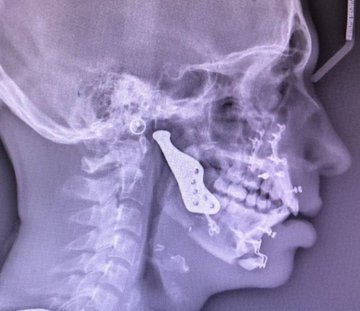

وقد اعتمد الفريق خطة جراحية من خلال ازالة التصلب العظمي في المفصل وقاع الجمجمه، وتعويضه بمفصل صناعي، صمم وصنع خصيصا باستخدام التخطيط الجراحي الافتراضي، ثلاثي الابعاد.

اضافه الى عملية تقويم جراحيه معقده لتقديم وتعديل ميلان الفك السفلي وتقديم الفك العلوي والذقن. وقد تكللت جهود الفريق بالنجاح ولله الحمد..